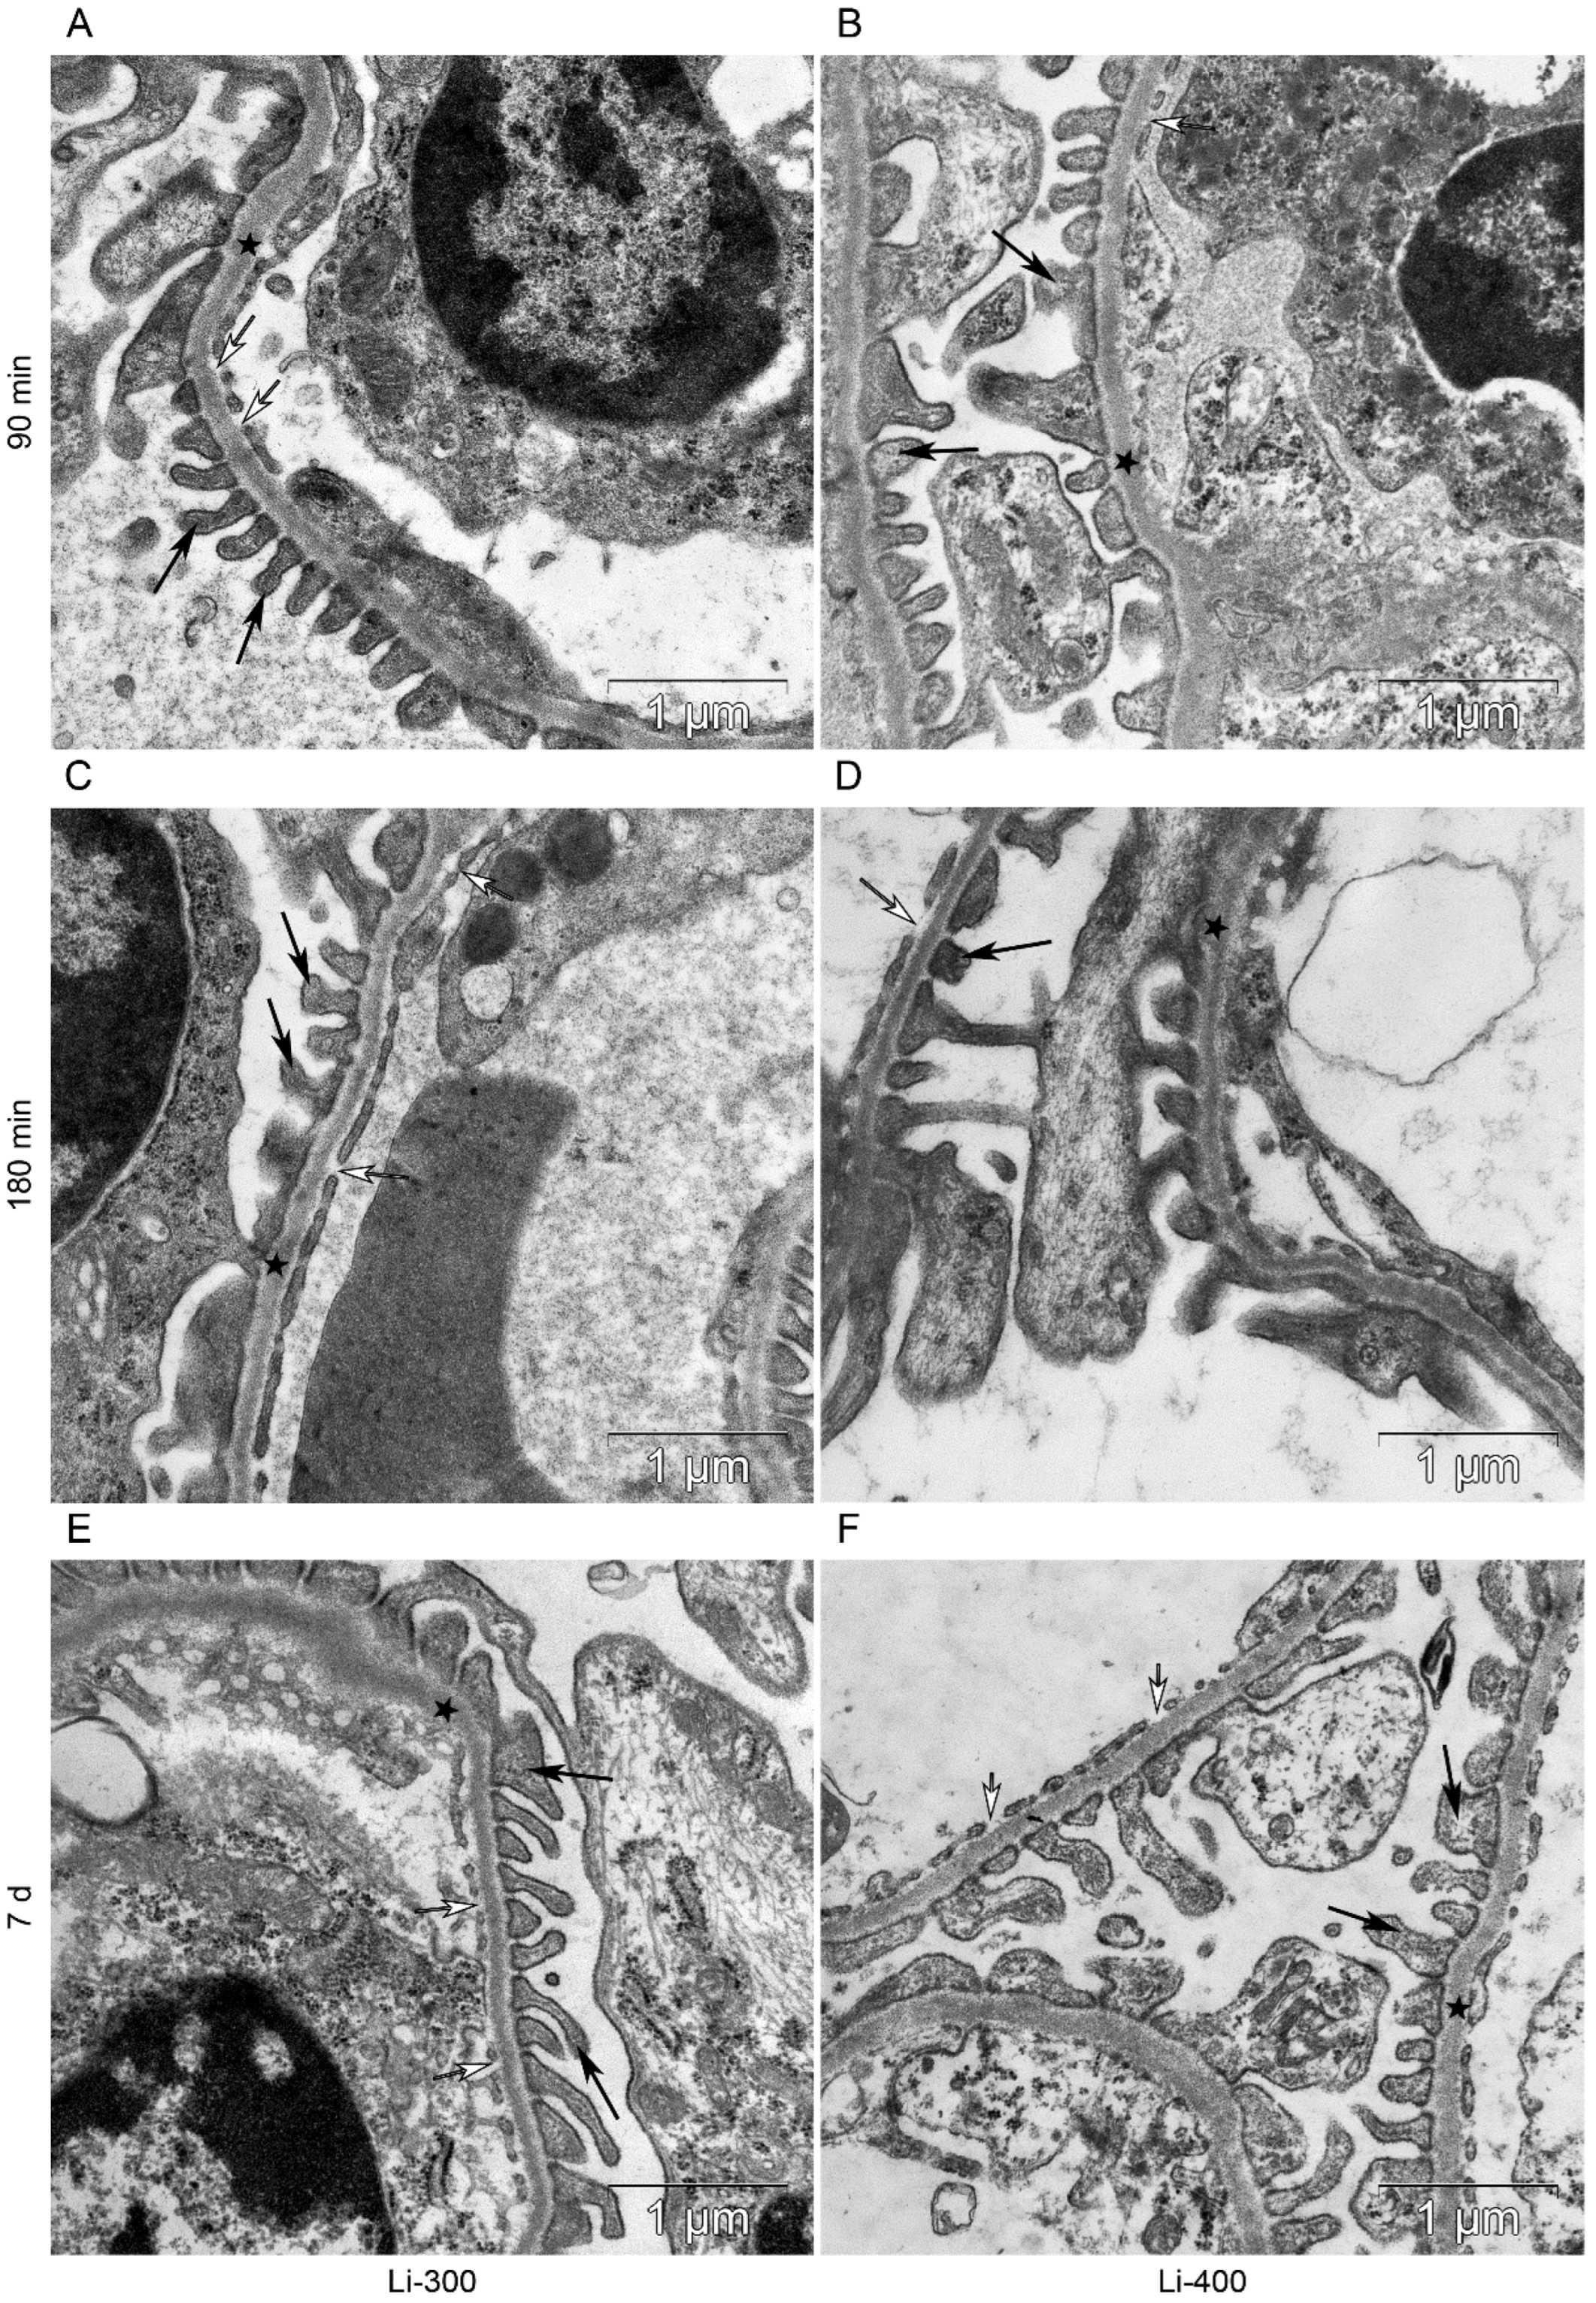

All components of the mice kidney filtration barrier in the control group had a typical ultrastructural organization (Figure 6). Fenestrae of endotheliocytes of glomerular capillaries were well expressed. The heterogeneity of the ultrastructural organization of podocytes was noted. Podocyte foot processes often varied in thickness. The glomerular membrane and basement membrane of proximal tubular epitheliocytes had equable density and thickness. Lithium administration at a single dose of 300 mg/kg and 400 mg/kg did not lead to a significant change in the structure of the kidney filtration barrier (Table 4; Figure 7 and Figure 8). There were no statistically significant differences between the lithium-treated and control groups.

Figure 7.

The kidney filtration barrier structure at (A,B) 90 min, (C,D) 180 min and (E,F) 7 d after peroral lithium carbonate administration at single doses of 300 (Li-300) and 400 (Li-400) mg/kg. Glomerular basement membrane (asterisks); podocyte foot processes (black arrows); fenestrae of endotheliocytes of the glomerular capillary (white arrows).